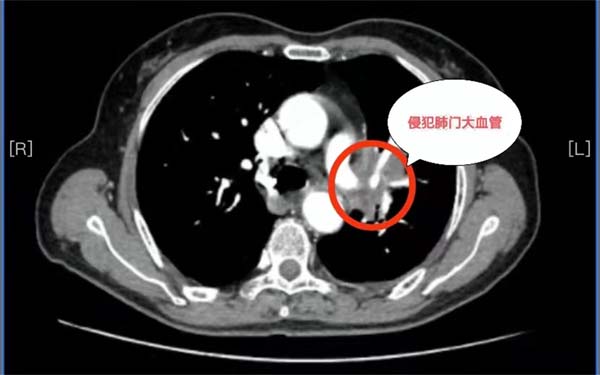

历经波折后求医无果,经多方打探,抱着最后一线希望杨女士和家人来到应急总医院胸外科求诊。胸外科副主任杨龙海博士从事胸外科专业多年,在肺癌方面具有丰富的诊治经验。杨龙海博士凭借丰富的临床经验,结合外院检查结果,排除远处转移,判断患者有手术的机会,且肺癌根治性手术远期效果相对较好,有治愈的可能。然而,肿瘤发现时已局部晚期,肿块巨大,侵犯到了左肺门大血管,侵犯纵隔及胸壁,加上患者伴有20多年的支气管扩张病史,致使患者症状较重,活动后气喘。这些因素导致手术需要切除整个左肺,手术难度及风险极高,切除过程会遇到肿瘤与肺门、纵隔、心包、胸膜等分离困难的难题,如果处理不当,可能出现大出血、循环呼吸衰竭等严重情况,随时危及生命。

经过精心准备,患者于入院的第5天顺利完成了根治性切除手术,虽然手术中,由于瘤体过大压迫心脏,患者一度出现了低血压等紧急情况,但在麻醉科和胸外科等多学科团队的共同努力下转危为安,手术圆满完成。术后患者恢复良好,第二天就能下床活动,术后一周康复出院。